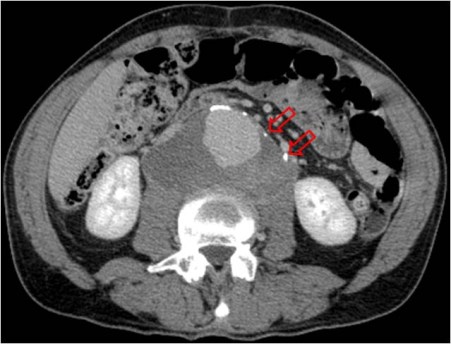

SIGNO DEL CALCIO TANGENCIAL

Consiste en el desplazamiento del calcio de la pared aórtica, que se sitúa por fuera de la esperada circunferencia del aneurisma. En ocasiones, en aortas muy calcificadas, puede verse también una interrupción del anillo calcificado, con los márgenes abiertos, asimismo apuntando hacia fuera de la circunferencia. Corresponde a un punto de debilidad de la pared y suele ser el sitio de rotura.

Se trata, pues, de otro signo de rotura contenida o inminente. La imagen es del mismo paciente del signo anterior, ésta en fase portal. Obsérverse como los calcios intimales (flechas) están desplazados.